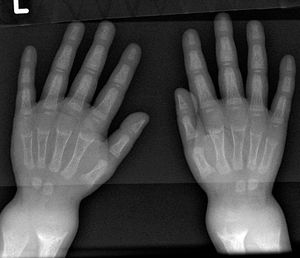

어린아이는 O다리와 두꺼워진 발목과 손목이 있을 수 있으며,[17] 나이가 많은 아이는 안짱다리가 있을 수 있다.[14] 척추 측만증 또는 요추 척추전만증의 척추 만곡이 나타날 수 있다. 골반뼈가 변형될 수 있다. 구루병 염주는 늑골연골관절에 형성되는 결절로 인한 두꺼워짐으로 인해 발생할 수 있다. 이는 몸의 양쪽에 선을 따라 각 늑골의 중앙에 보이는 혹으로 나타나며, 묵주와 비슷하여 그 이름이 붙었다. 비둘기 가슴[14]의 변형으로 해리슨의 홈이 나타날 수 있다.

X선 또는 방사선 사진은 구루병의 고전적인 양상(O다리, 변형된 가슴)을 보여준다. 두개골의 변화도 발생하여 "사각형 머리" 모양인 "사각두"가 나타난다.[18] 이러한 변형은 치료하지 않으면 성인기에도 지속된다. 장기적인 결과로는 장골의 영구적인 만곡 또는 변형과 굽은 등이 있다.[19]

- 방사선 사진에서는 일반적으로 석회화되지 않은 골기질로 인해 일시적 석회화 영역이 넓어지는 것을 보여준다. 컵 모양 변형, 섬유화, 골단의 벌어짐은 성장과 지속적인 체중 부하와 함께 나타난다.[47] 이러한 변화는 상완골 근위부, 요골 원위부, 대퇴골 원위부, 경골 근위부와 원위부를 포함한 빠른 성장 부위에서 주로 관찰된다. 따라서 구루병에 대한 골격 전반 검사는 무릎, 손목 및 발목의 전후 방사선 사진으로 수행할 수 있다.[47]